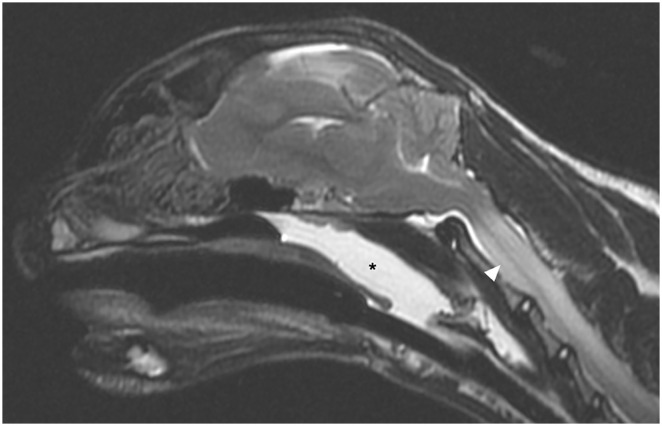

Case summary: A 4-year-old female neutered Scottish Fold shorthair cat was presented for further investigation of circling towards the right. MRI of the brain revealed an extensive, right-sided temporal muscle lesion with associated frontotemporal bone osteolysis, intracranial, extra-axial extension along the calvarial convexity with severe pachy- and leptomeningeal thickening and contrast enhancement, and an intra-axial space-occupying lesion in the right piriform lobe. The regional lymph nodes were moderately enlarged. Cytology of the right parotid lymph node and the temporal muscle was performed and histiocytic sarcoma (HS) was diagnosed. The owners elected euthanasia.

Relevance and novel information: HS of the central nervous system (CNS) is a very rare neoplastic condition in cats. Although a few case reports mention MRI, to our knowledge, the characterisation of MRI features of feline CNS HS have not been investigated in detail. Therefore, the aim of this case report was to describe the MRI characteristics in a feline HS involving not only the CNS, but also the fronto-temporal bone, temporal muscle and the regional lymph nodes. In particular, aggressive neoplastic bone invasion was a novel finding.